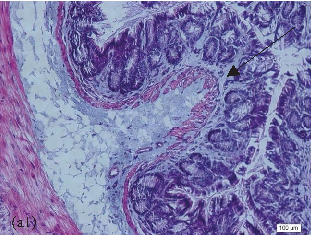

- FIGURE 2: Histopathological analysis of the colon related tothe experimental group: control group(a, a1), colitis group (b, b1),andN-acetylcysteine (NAC) group (c, c1). Representative photomicrographs of mouse colonic sections. Black arrow, preservation of the crypt structure; black dashed arrow, crypt destruction; and black dotted arrow, narrowing of the mucosal muscle. 10x magnification. Hematoxylin and eosin (HE) staining.

- 3.1. Histological Analysis of the Colon. Histological evaluation showed changes in colon architecture related to colitis, including destruction, disarrangement, and shortening of the crypts, indicating that the administration of DSS induced UC in mice (Figure 2(b)), when compared to the control (Figure 2(a)). NAC administration partially restored the epithelial structure, as indicated by the intact areas in the histological section (Figure 2(c)).